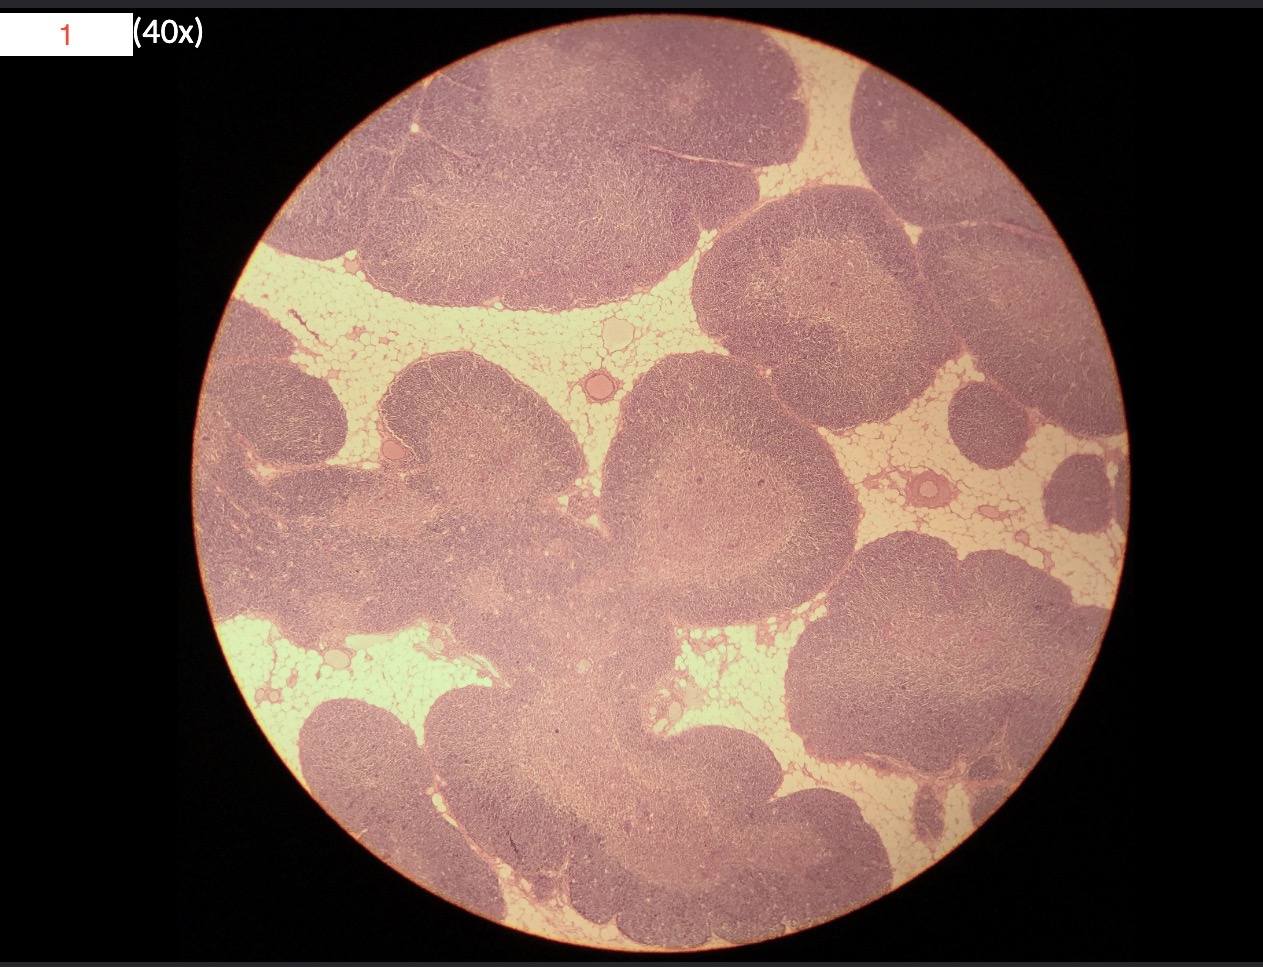

1 - What is this slide

Spleen

2

White pulp

3

Red pulp